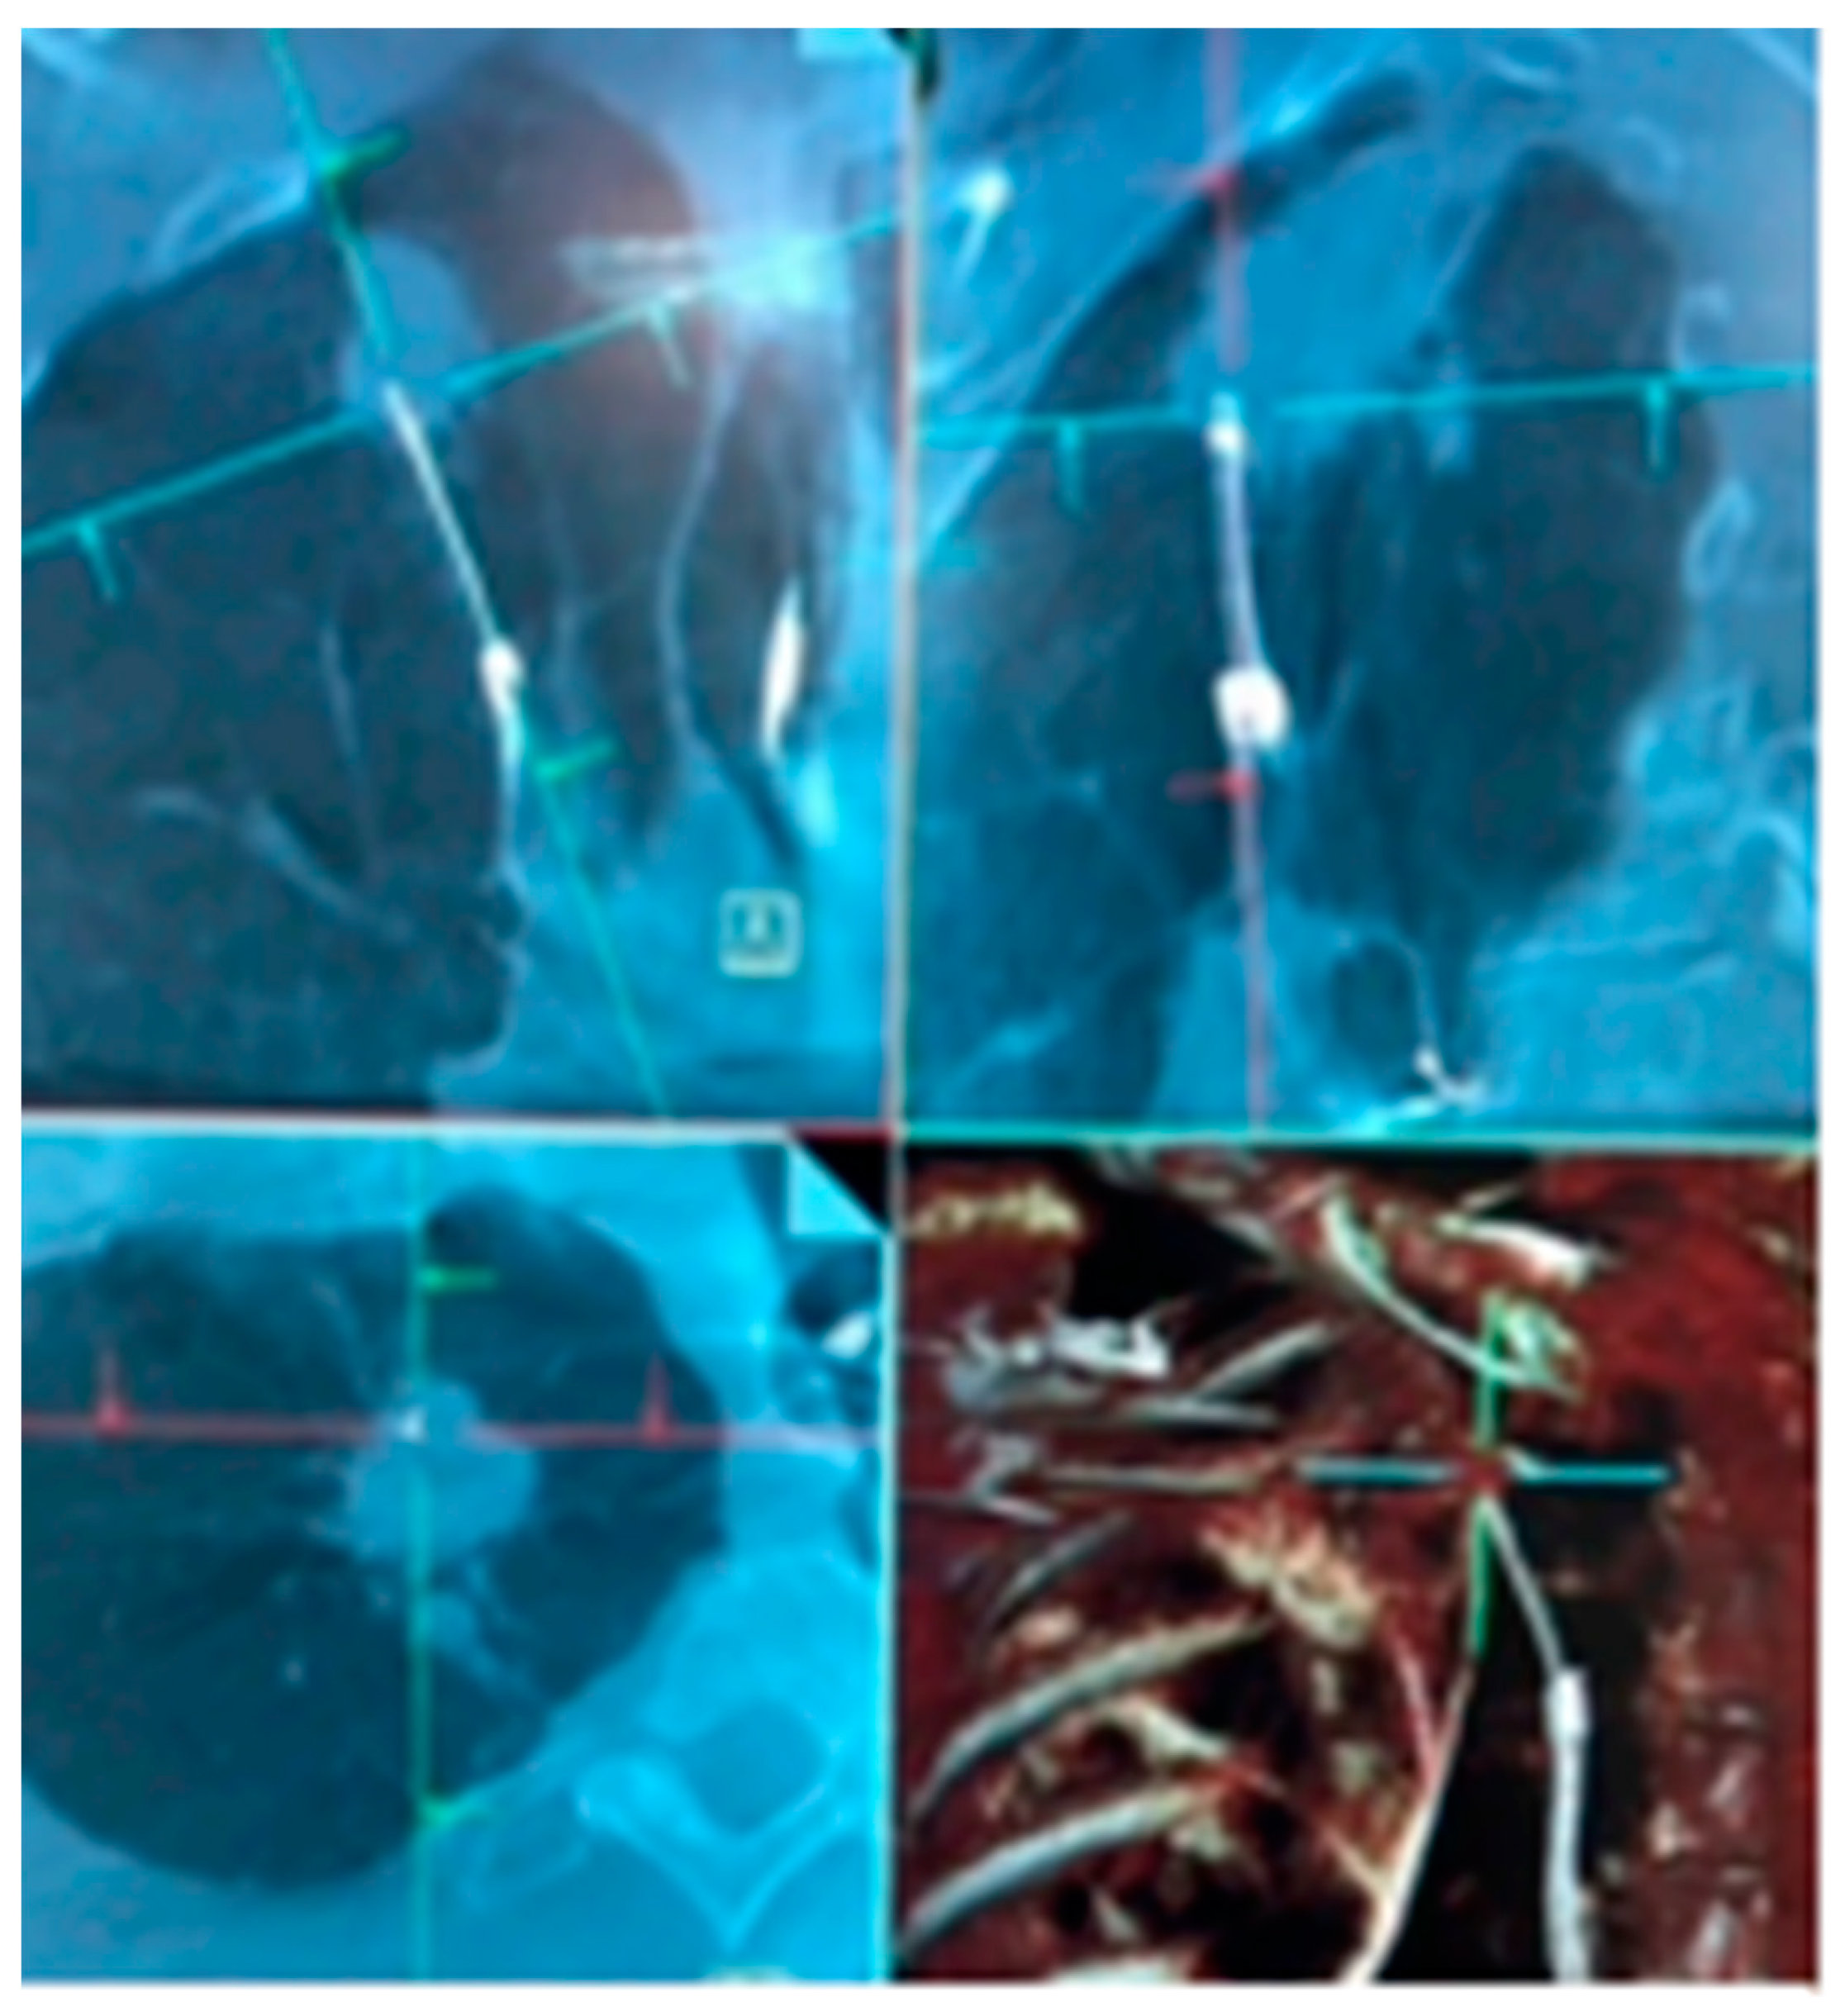

- Chan, J.W.Y.; Chang, A.T.C.; Yu, P.S.Y.; Lau, R.W.H.; Ng, C.S.H. Robotic Assisted-Bronchoscopy with Cone-Beam. CT ICG Dye Marking for Lung Nodule Localization: Experience Beyond USA. Front. Surg. 2022, 9, 943531. [Google Scholar] [CrossRef] [PubMed]